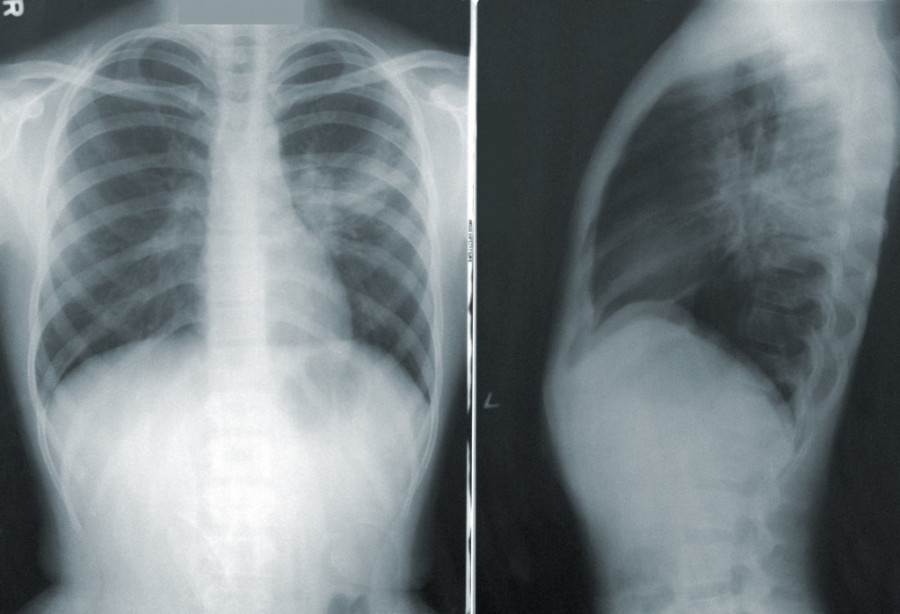

- Možda ste videli te teške slike iz crvenih zona gde pacijente okreću na stomak. Za to treba da bude izuzetno obučen tim, posebno ako je pacijent intubiran. Zašto se to radi? Zato što se na taj način zadnji delovi pluća na koje kada se leži na leđima naležu srce i drugi organi budu manje ventilirani i ishranjeni - navodi Stefanović.

- Svaka virusna infekcija, pa i kovid zahteva mirovanje. Ako se lečite u kućnim uslovima potrudite se da najviše vremena provedete u polusedećem položaju i spavate na stomaku. Na taj način se ventiliraju i oni delovi pluća koji su inače pod pritiskom. To je put do bržeg ozdravljenja - objasnila je Stefanović.